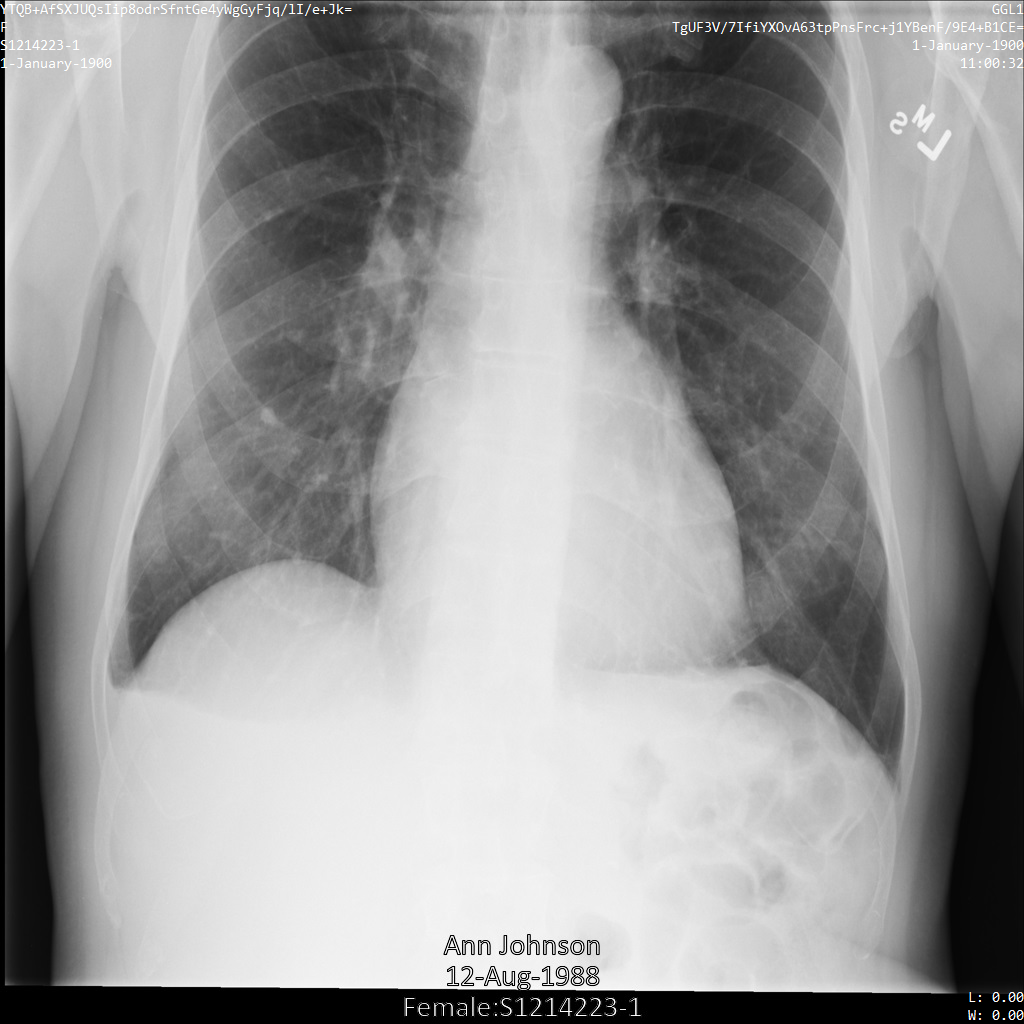

以下各節提供範例,說明如何使用各種方法去識別 DICOM 資料。每個樣本都會提供去識別化圖片的輸出內容。每個範例都會使用下列原始圖片做為輸入內容:

您可以比較各項去識別化作業的輸出圖片與原始圖片,瞭解作業效果。

將圖片提交給 Cloud Healthcare API 後,圖片會如下所示。雖然圖片頂端角落顯示的中繼資料已遭塗銷,但圖片底部的內建受保護健康資訊 (PHI) 仍存在。如要一併移除內建文字,請參閱「從圖片中遮蓋內建文字」。

下圖顯示未經過編輯的病患 X 光片:

使用 REDACT_SENSITIVE_TEXT 選項將圖片提交給 Cloud Healthcare API 之後,圖片看起來會如下所示:

您可以看到發生了下列情況:

- 圖片左下角的

PERSON_NAME已遭塗銷 - 圖片左下角的

DATE已遭塗銷

由於根據預設 DICOM infoTypes,病患性別不屬於敏感文字,因此未經過修訂。